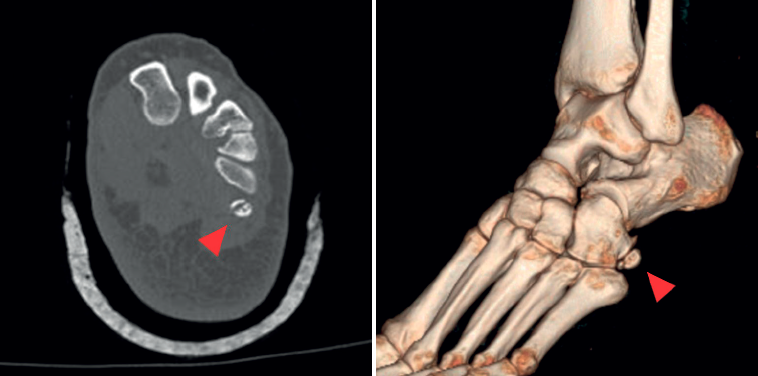

Se realizaron radiografías bilaterales del pie que evidenciaron la presencia de OP bilateral, con irregularidad en el margen del OP derecho. Inicialmente, se sospechó fractura del hueso cuboides (Figura 1); sin embargo, una tomografía computarizada (TC) descartó dicha fractura e identificó un trazo de fractura en el OP derecho, sin desplazamiento (Figura 2). Se realizó resonancia magnética (RM) del pie derecho que confirmó edema en OP del TPL, no desplazada ni complicada. TPL íntegro.

En el caso presentado se sospechó radiográficamente fractura del hueso cuboides, por lo que se indicó TC que informó fractura no desplazada de OP. El uso combinado de radiografías bilaterales (Figura 4) y TC (Figura 2) permitió diferenciar la presencia de variantes anatómicas como el OP, además de distinguir un OP bipartito de una fractura de este.